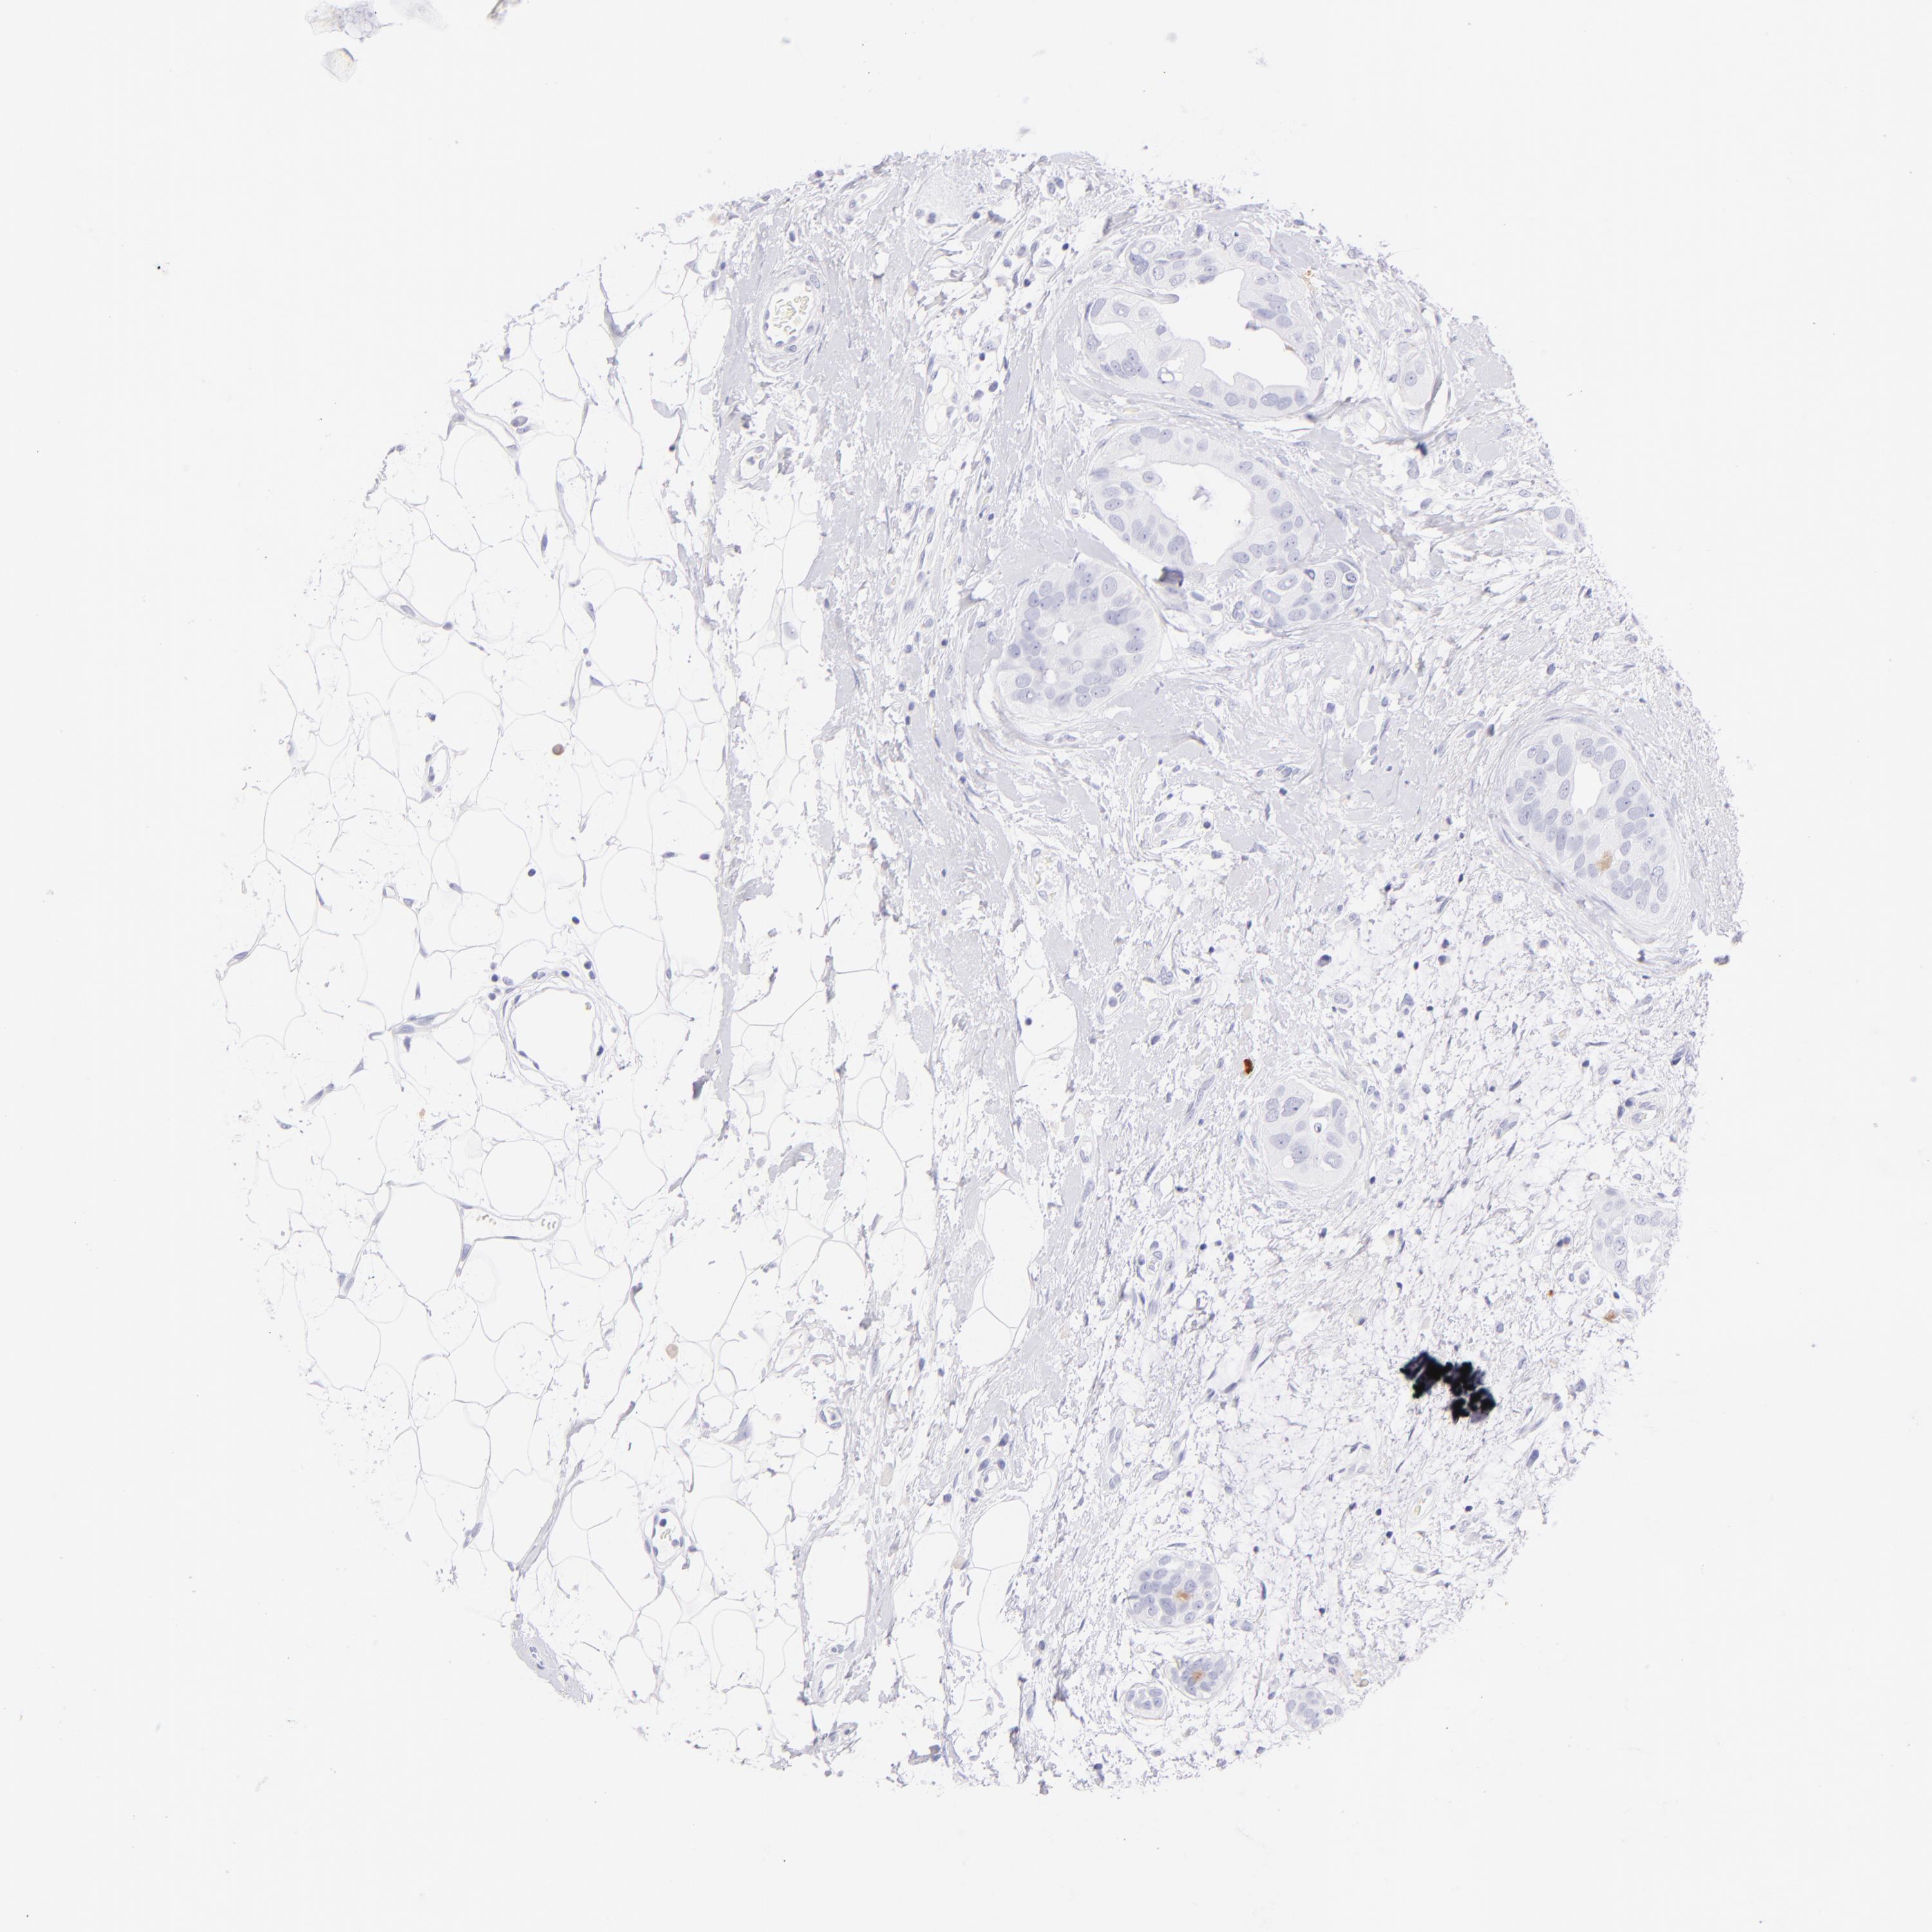

BRCA TCGA BRCA VALIDATION PROTEIN EXPRESSION

ANTIBODIES

AND

VALIDATION